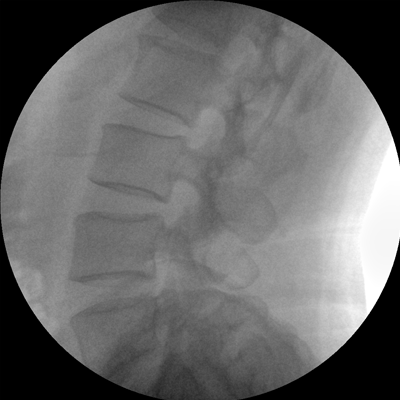

數(shù)字高清影像  助力臨床診斷

專業(yè)的圖像處理系統(tǒng),為您提供高分辨率、高灰階圖像。

Clinical picture

臨床圖片